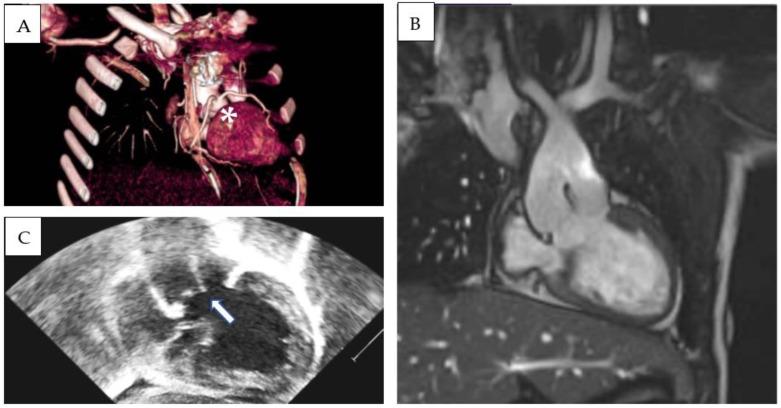

Double-outlet left ventricle (DOLV) is an abnormal ventriculo-arterial connection characterized by the origin of both great arteries from the morphological left ventricle. The aim of our paper is to describe the morphological and imaging features of DOLV and to assess the prevalence of the associated malformations and their surgical outcomes. METHODS From 2011 to 2022, we retrospectively reviewed the electronic case records of patients diagnosed with DOLV at the Bambino Gesu Children's Hospital. A systematic search was developed in MEDLINE, Web of Science, and EMBASE databases to identify reports assessing the morphology and outcomes of DOLV between 1975 and 2023. RESULTS: Over a median follow-up of 9.9 years (IQR 7.8-11.7 y), four cases of DOLV were identified at our institution. Two patients were diagnosed with (S,D,D) DOLV subaortic VSD and pulmonary stenosis (PS): one patient had (S,D,D) DOLV with doubly committed VSD and hypoplastic right ventricle, and another patient had (S,D,L) DOLV with subaortic VSD and PS (malposition type). Pulmonary stenosis was the most commonly associated lesion (75%). LITERATURE REVIEW: After systematic evaluation, a total of 12 reports fulfilled the eligibility criteria and were included in our analysis. PS or right ventricular outflow tract obstruction was the most commonly associated lesion (69%, 95% CI 62-76%). The most common locations of VSD were subaortic (pooled prevalence: 75%, 95% CI 68-81), subpulmonary (15%, 95% CI 10-21), and doubly committed (7%, 95% CI 4-12). The position of the great arteries showed that d-transposition of the aorta was present in 128 cases (59% 95% CI 42-74), and l-transposition was present in 77 cases (35%, 95% CI 29-43).

双出口左心室(DOLV)是一种异常的心室-动脉连接,其特征为两大动脉均起源于形态学上的左心室。本文的目的是描述双出口左心室的形态学和影像学特征,并评估相关畸形的患病率及其手术结果。方法:2011年至2022年,我们回顾性分析了在 Bambino Gesu儿童医院诊断为双出口左心室的患者的电子病历。在 MEDLINE、科学网和 EMBASE数据库中进行了系统检索,以识别 1975年至 2023年期间评估双出口左心室形态学和结果的报告。结果:在中位随访 9.9年(四分位间距 7.8 - 11.7年)期间,我们机构共识别出 4例双出口左心室患者。2例患者被诊断为(S,D,D)型双出口左心室合并主动脉下室间隔缺损和肺动脉狭窄(PS):1例患者为(S,D,D)型双出口左心室合并双室连接室间隔缺损和右心室发育不良,另 1例患者为(S,D,L)型双出口左心室合并主动脉下室间隔缺损和 PS(位置异常型)。肺动脉狭窄是最常见的相关病变(75%)。文献综述:经过系统评估,共有 12篇报告符合纳入标准并纳入我们的分析。肺动脉狭窄或右心室流出道梗阻是最常见的相关病变(69%,95%CI 62 - 76%)。室间隔缺损最常见的位置是主动脉下(合并患病率:75%,95%CI 68 - 81)、肺动脉下(15%,95%CI 10 - 21)和双室连接(7%,95%CI 4 - 12)。大动脉的位置显示,128例(59%,95%CI 42 - 74)存在主动脉 d-转位,77例(35%,95%CI 29 - 43)存在 l-转位。